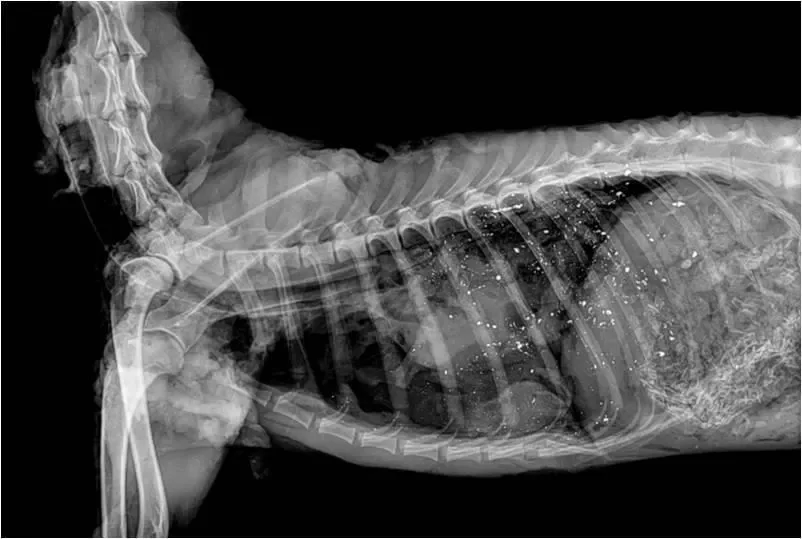

Gut Pile Radiographs

X-ray imaging of discarded gut piles reveals lead fragments concentrated in the organs — the exact remains that scavenging wildlife depends on for food.